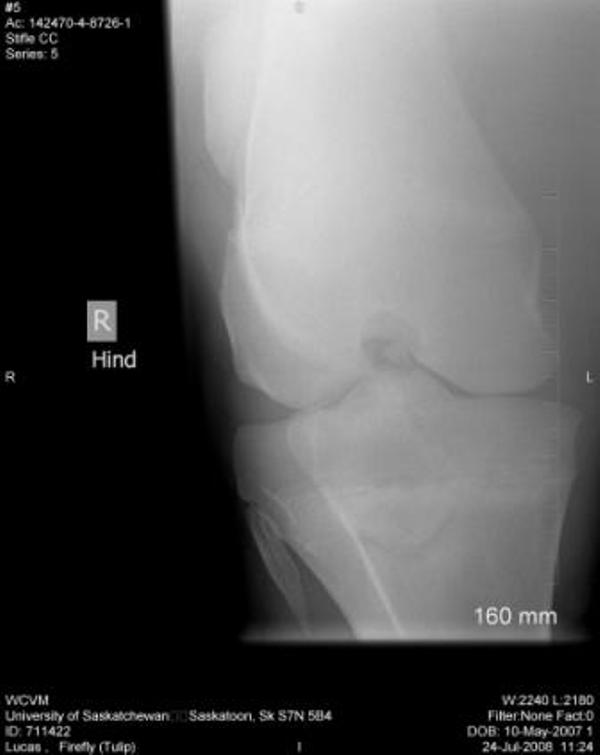

Right stifle

Thanks Dr. O!! I really appreciate your taking a look at this. I do have Dr. Rantanen's report which is as follows:

Interpretation:

The most proximal portion of the right medial tibial spine was separated by an irregular fracture line. The fragment was still close to its anatomic position.

There was no soft tissue swelling or secondary joint disease present at this time.

Comment:

With the absence of clinical signs of lameness, normal flexion and no soft tissue swelling at this time, this fracture most likely occurred at a young age. It may be an incidental finding in this horse. Success in training would confirm that this fracture most likely occurred at a young age and may be tolerated without surgical intervention.